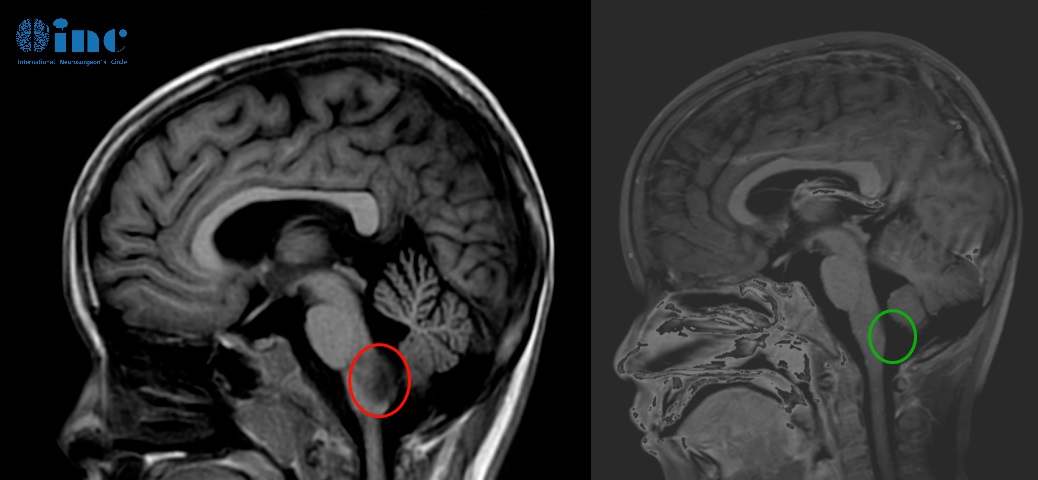

24岁男性-脑干延髓低级别胶质瘤

6岁男孩-延髓毛细胞星形细胞瘤

5岁女孩脊髓-脑干毛细胞星形细胞瘤

术后一年多,琦琦回归校园,她一直努力坚持做训练,运动是她每天的必修课,家里的沙发上、椅子旁、地板垫子上……随处可见她运动的身影!